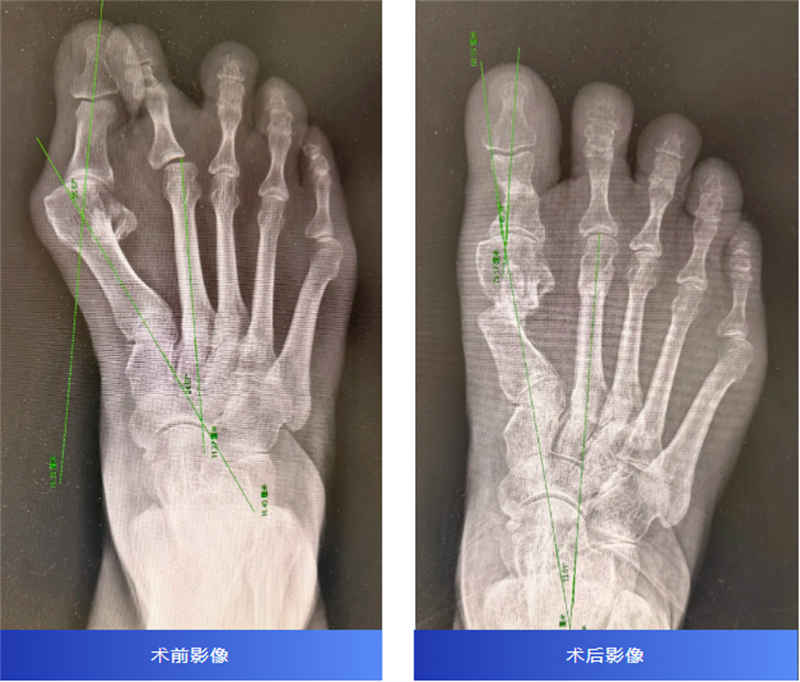

術后三個月復查X片顯示,截骨處已骨性愈合,足部外形得到改善,疼痛消失。韋釗嵐醫師鼓勵她:“可以逐漸恢復跑步和跳舞了!”聽到這個消息,王阿姨激動不已。